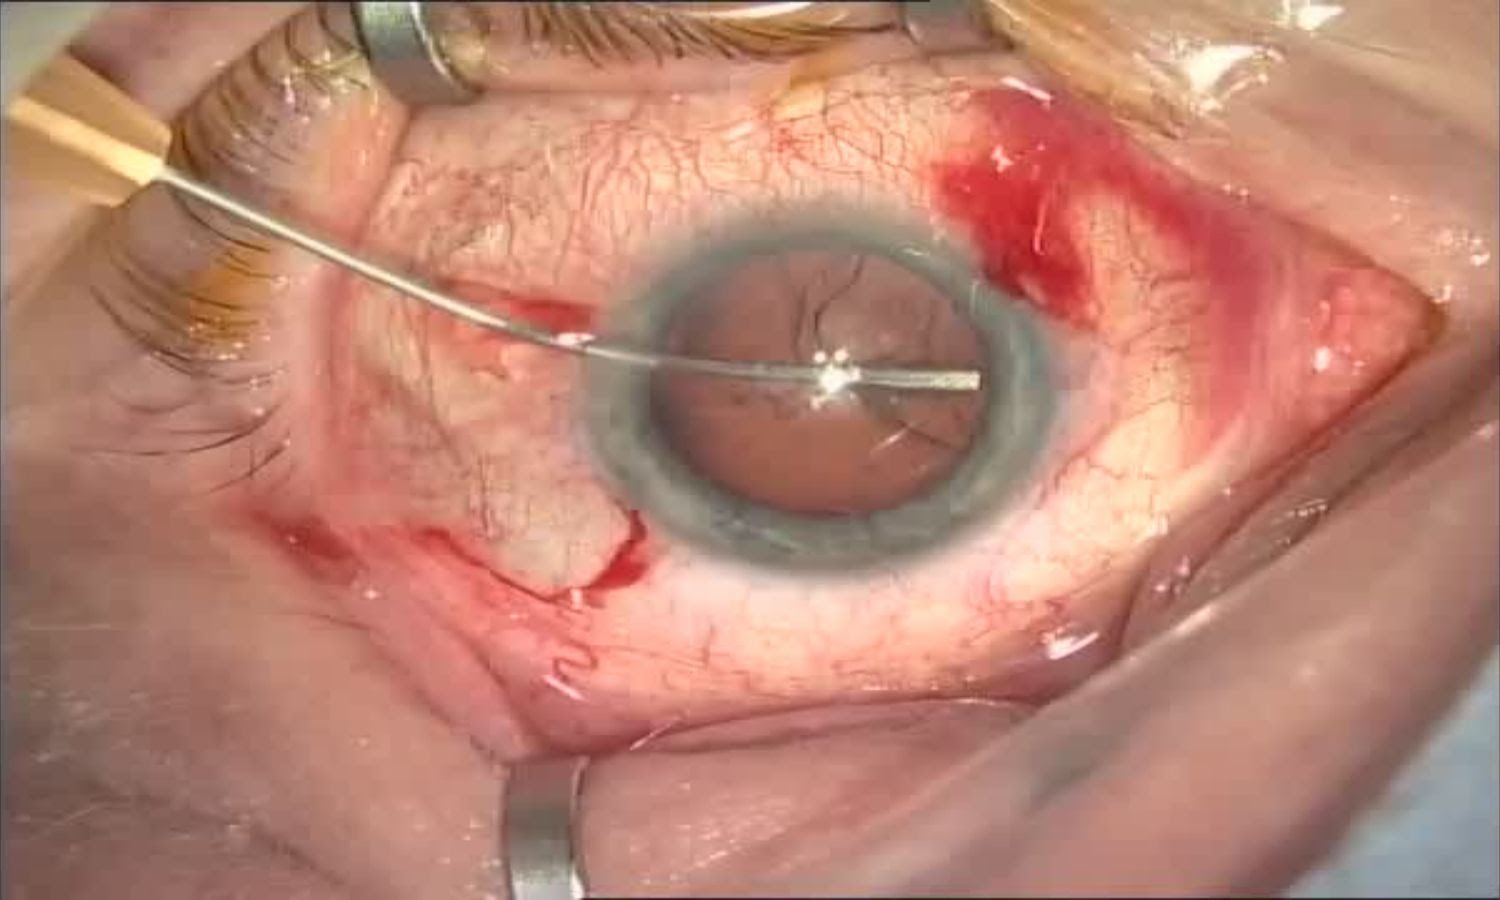

Несмотря на твёрдую (хрящеобразную) консистенцию, просто взять и вытащить хрусталик нельзя — сначала нужно «измельчить» его. Делается это специальной машиной — факоэмульсификатором. За счёт ультразвука он фрагментирует хрусталик до состояния «пюре» и «высасывает» его — как пылесосом с щелевой насадкой. Если хрусталик перезрелый и чёрного цвета, то звуки при удалении будут как у бормашины стоматолога. Если незрелый, начальный — всё проходит быстро, прибор всасывает частицы легко и ультразвука используется минимальное количество, а окружающие ткани (роговица, радужка, стекловидное тело) сохраняются здоровыми.

Вымывание кортикальных масс, то есть мягкой части — аспирация

Аспирация кортекса